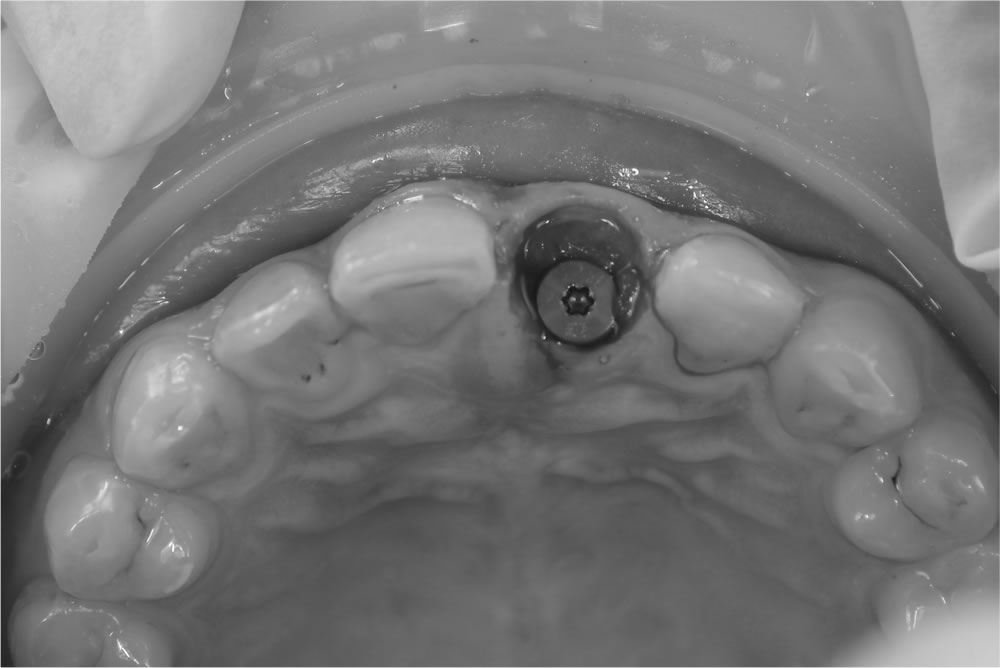

当該歯を部分的に抜歯(ソケットシールドテクニック)

ソケットシールドテクニックを用いて当該歯を部分的に抜歯しました。

上部構造(精密な仮歯)を作成・装着

歯茎の治癒を待ち、2ヵ月後に型取りしてインプラントの上部構造(精密な仮歯)を作成・装着しました。